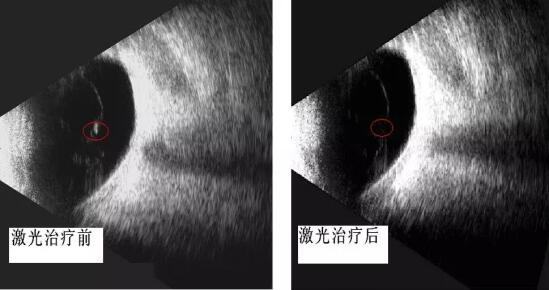

男同视频 眼科开启"灭蚊"时代 ――飞蚊症的治疗